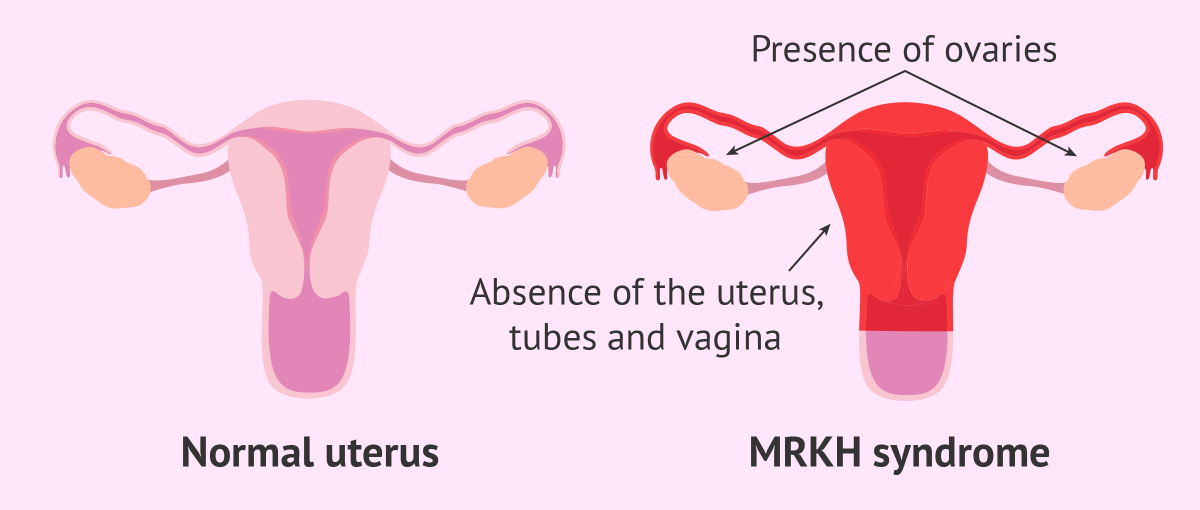

Questa malattia conosciuta anche come sindrome di Mayer-Rokitansky-Kuster-Hauser (MRKH) si caratterizzata per l’assenza congenita della vagina e dell’utero.

Le donne che ne sono affette nascono quindi senza vagina e utero, ma con ovaie e genitali esterni sviluppati normalmente.

Questo significa che lo sviluppo psico-fisico e lo sviluppo dei caratteri sessuali secondari, come il seno, la peluria pubica e conformazione della vulva sono assolutamente normali.